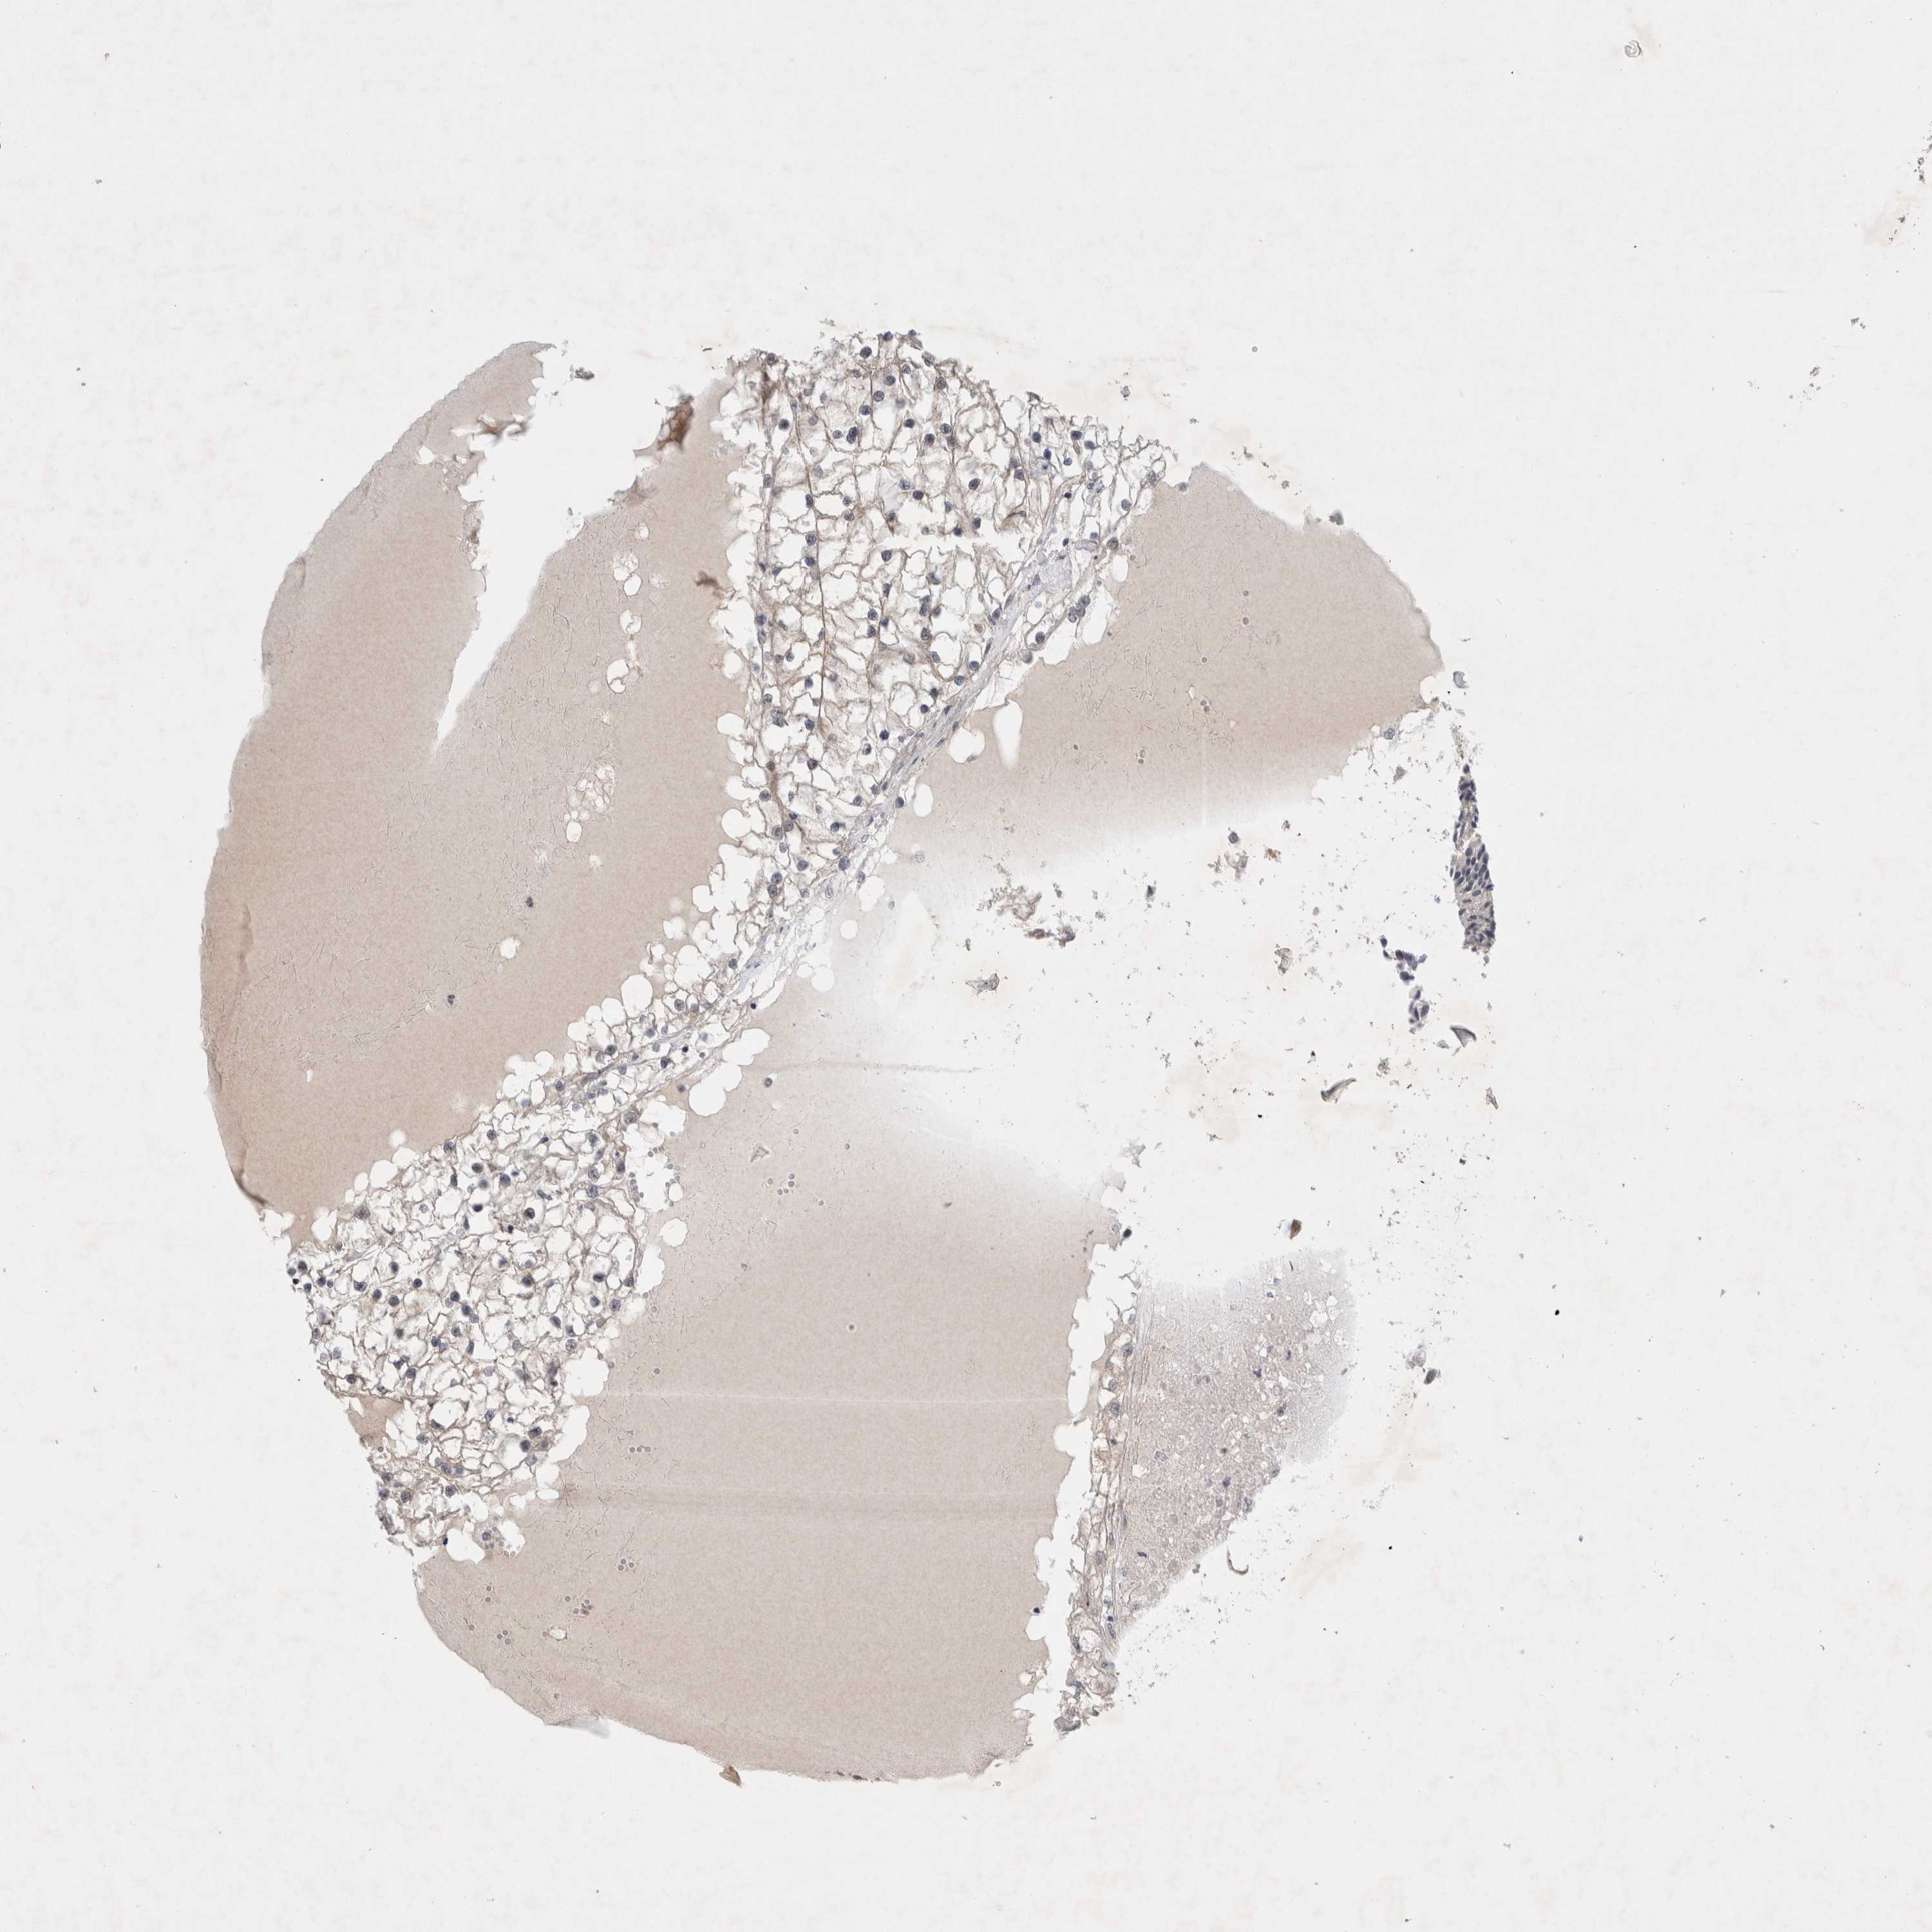

KIDNEY RENAL PAPILLARY CELL CARCINOMA (TCGA) - Interactive survival scatter ploti

The Survival Scatter plot shows the clinical status (i.e. dead or alive) for all individuals in the patient cohort, based on the same data that underlies the corresponding Kaplan-Meier plots. Patients that are alive at last time for follow-up are shown in blue and patients who have died during the study are shown in red.

The x-axis shows the expression levels (FPKM) of the investigated gene in the tumor tissue at the time of diagnosis. The y-axis shows the follow-up time after diagnosis (years). Both axes are complimented with kernel density curves demonstrating the data density over the axes. The top density plot shows the expression levels (FPKM) distribution among dead (red) and alive patients (blue). The right density plot shows the data density of the survived years of dead patients with high and low expression levels respectively, stratified using the cutoff indicated by the vertical dashed line through the Survival Scatter plot. This cutoff is automatically defined based on the FPKM cutoff that minimizes the p-score. The cutoff can be changed by dragging the vertical line or by entering a cutoff value in the square labeled "Current cut-off".

Under the Survival Scatter plot the p-score landscape (black curve; left axis) is shown together with dead median separation (red curve; right axis). Dead median separation is the difference in median mRNA expression between patients who have died with high and low expression, respectively. It is calculated as follows: median FPKM expression of dead patients with high expression - median FPKM expression of dead patients with low expression. This is intended to aid the user in visually exploring custom cutoffs and the associated p-scores and dead median separation.

Individual patient data is displayed and can be filtered by clicking on one or more of the category buttons on the top of the page. Categories describing expression level and patient information include: high, low, alive, dead, female, male and tumor stages. The scale of the x-axis can be toggled between linear and log-scale by clicking on the "x log" button. Mouse-over function shows TCGA ID, patient information and mRNA expression (FPKM) for each patient.

& Survival analysisi

Kaplan-Meier plots summarize results from analysis of correlation between mRNA expression level and patient survival. Patients were divided based on level of expression into one of the two groups "low" (under cut off) or "high" (over cut off). X-axis shows time for survival (years) and y-axis shows the probability of survival, where 1.0 corresponds to 100 percent.

WIPF2 is not prognostic in Kidney Renal Papillary Cell Carcinoma (TCGA)

Best expression cut offi

Based on the FPKM value of each gene, patients were classified into two groups and association between prognosis (survival) and gene expression (FPKM) was examined. The best expression cut-off refers the FPKM value that yields maximal difference with regard to survival between the two groups at the lowest log-rank P-value. Best expression cut-off was selected based on survival analysis .

When clicking on this number, the vertical dashed line indicating cut-off, the interactive survival plot, and the Kaplan-Meier curve will be adjusted to show results based on the best expression cut-off.

: 18.95